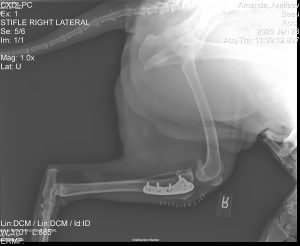

This type of an injury is a mechanical lameness and surgery is generally recommended quickly to reduce pain and prevent permanent change to the joint. One such surgical technique to help stabilize the knee joint is Tibial Plateau Leveling Osteotomy (TPLO). TPLO surgery changes the angle of the tibia to the femur, therefore reducing the sliding or draw in the knee joint, stabilizing the knee and preventing osteoarthritis.

Healing from TPLO surgery is generally quick. Most dogs are walking or toe touching on the leg 24hrs post surgery and can be back to full activity by 3-6 months after.

Included in all of our TPLO and orthopedic surgeries, we use a Class IV laser on all animals. The laser treatment reduces pain and inflammation, thus allowing for the use of less medication and it also helps decrease recovery time. Each animal stays 3-5 days post-surgery to allow for us to do laser therapy with them. Also so the animals are better recovered for when they go home.